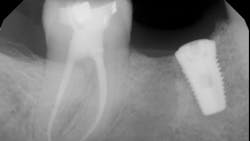

- The type of endodontic treatment dictates the length of healing. Nonsurgical endodontic treatment has a usual healing time of three months. Surgical intervention such as an apicoectomy due to large lesion size can take six to 12 months to heal (figures 1 and 2).